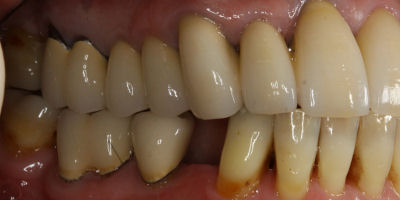

Before/After